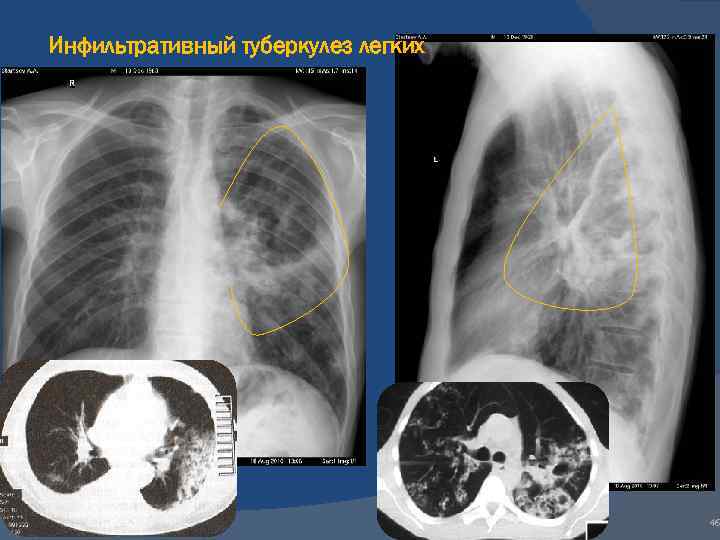

Иллюстрации по теме очагового и инфильтративного туберкулеза